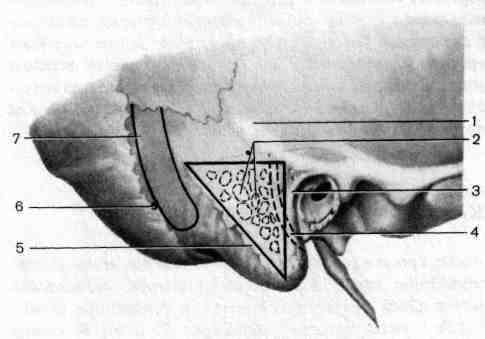

КТ анатомия сосцевидного отростка: особенности и показания